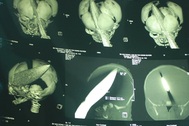

Sáng 14-8, ThS-BS Đào Trung Hiếu, Phó Giám đốc BV Nhi đồng 1, cho biết bé sơ sinh bị đâm dao vào đầu (bé Dương Minh Phát), con của chị Võ Thị Hồng Duyên (33 tuổi, Vĩnh Long) đã được cai máy thở và bé đã tự thở được, bé cũng đã được giảm liều kháng sinh.

Theo BS Hiếu, hiện bé Phát có thể co duỗi tay, chân, mắt mở. Đến thứ 2 tuần sau, BV sẽ tiến hành đánh giá lại. Như vậy sau 7 ngày nhập viện, tình trạng sức khoẻ bé tiến triển rõ rệt.